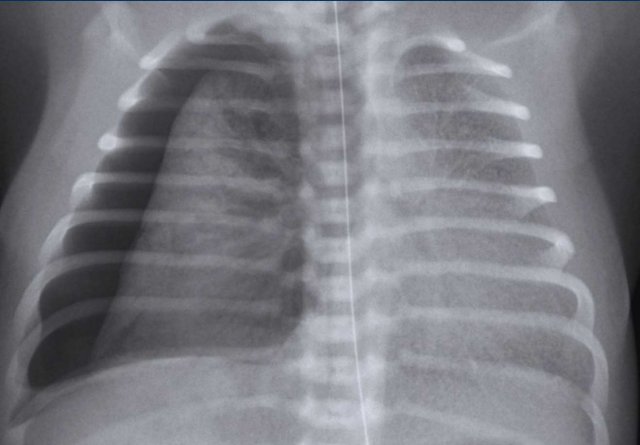

Chest film of a full term newborn with meconium stained amniotic fluid.

Image

• Hyperinflation

• Course diffuse patchy consolidations on both sides.

• Some subtle pleural fluid on both sides (arrowheads).

• Good position ETT. Superficial position NG tube, still in esophagus.

• Deep position of umbilical vein line with tip in right atrium.